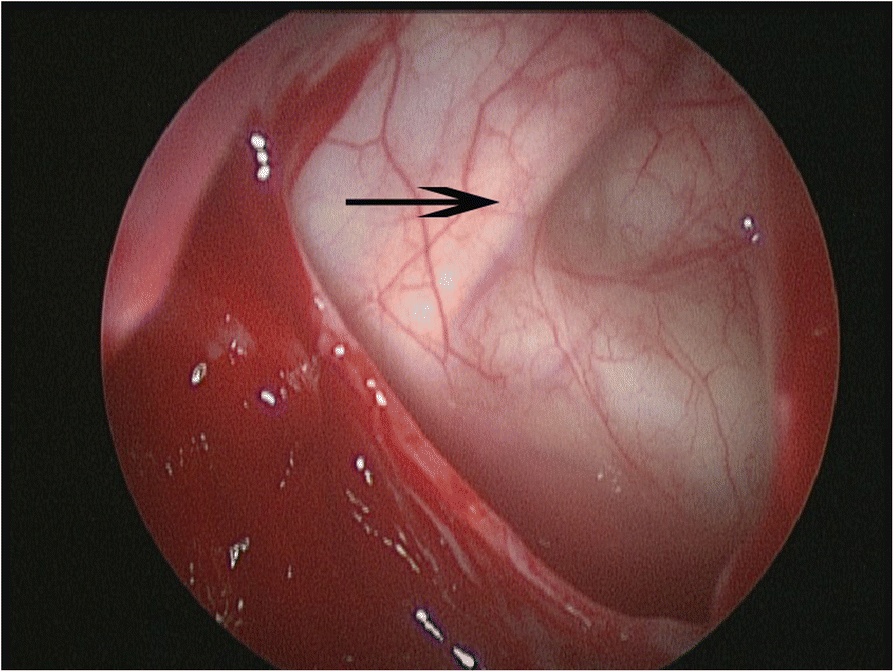

Fig. 4From: Is orbital floor a reliable and useful surgical landmark in endoscopic endonasal surgery?: a systematic reviewEndoscopic view of infraorbital nerve course at the orbital floor after maxillary anstrostomyBack to article page